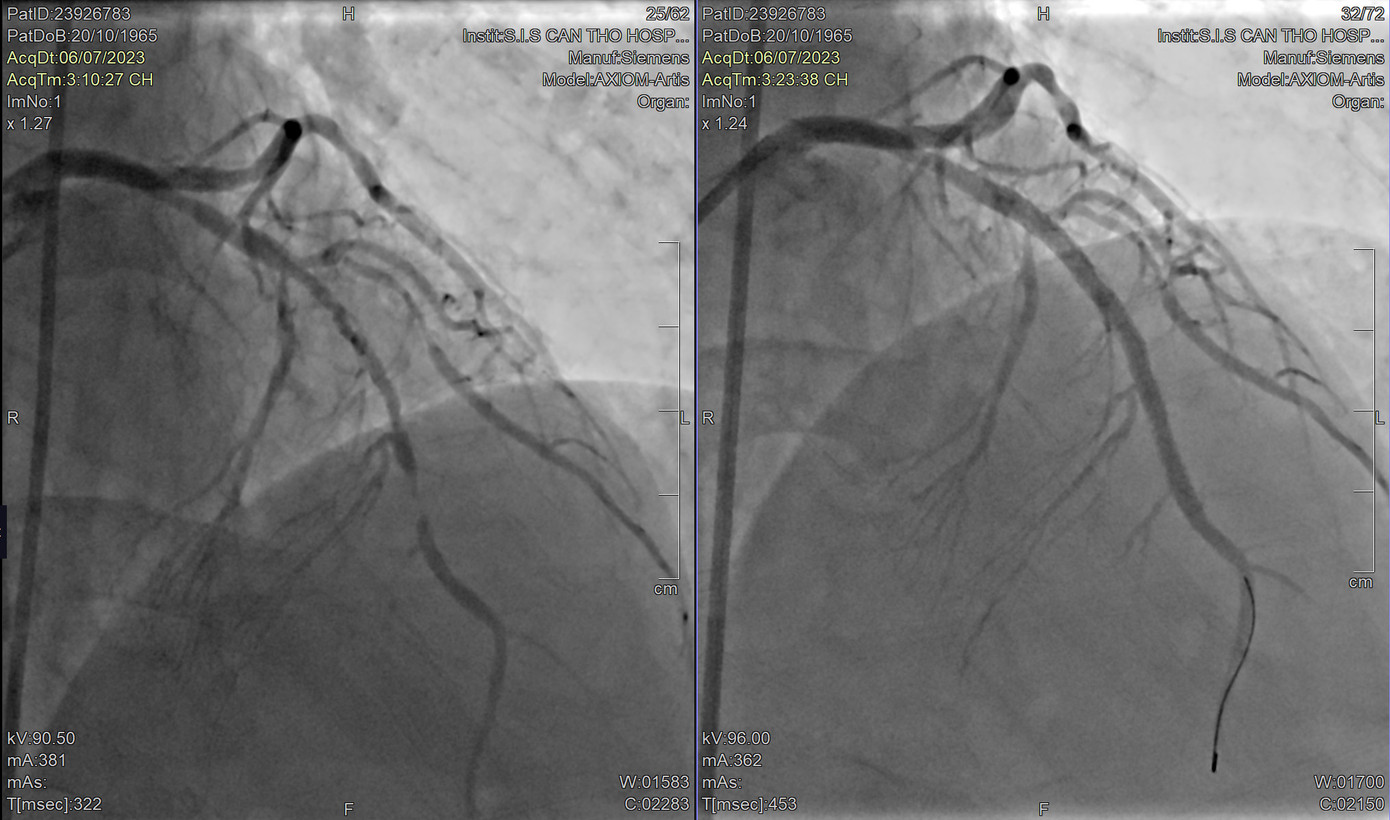

| Động mạch vành của bệnh nhân trước can thiệp bị tắc nghẽn, sau can thiệp được tái thông hoàn toàn |

Tại đây, kết quả điện tim cho thấy bệnh nhân bị nhồi máu cơ tim cấp gây tắc động mạch vành, nguy kịch tính mạng. Ngay lập tức, người bệnh được chuyển đến phòng can thiệp DSA. Sau khi can thiệp khẩn nguy, các bác sĩ đã đặt thành công stent tái thông vị trí động mạch vành nuôi tim, giúp bệnh nhân qua cơn nguy kịch, sức khỏe nhanh chóng bình phục.